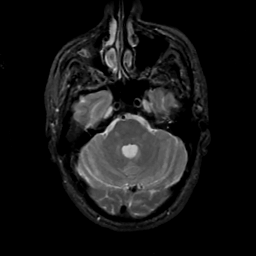

MR Study #14, June 2, 1991 -- Slice #13

[Home][Help][Clinical][Tour 1][Tour 2] Slice 13